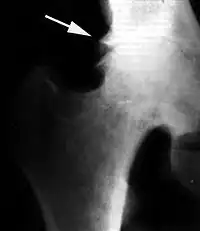

Исход артроза — полное разрушение сустава с формированием анкилоза — полной неподвижности сустава или неоартроза с неестественной подвижностью. Это сопровождается тяжёлым нарушением функции конечности. В последнее время, не дожидаясь исхода заболевания, всё чаще применяют специальные операции по замене сустава протезом — эндопротезирование сустава. На рисунке изображена типичная для терминальной стадии артроза коленного сустава варусная деформация колена в сочетании с боковой патологической нестабильностью коленного сустава. Артроз блоковидного или шаровидного сустава, такого как тазобедренный, завершается анкилозированием. При этом замыкание сустава обычно происходит в нефизиологическом (порочном) положении конечности. В данном случае мы видим бедро в положении сгибания и приведения, при котором нога укорачивается, а ось конечности и биомеханика опорно-двигательной системы существенно нарушается.

Рентгенологическая семиотика остеоартроза складывается из признаков, отражающих дистрофические изменения в суставных хрящах (сужение суставной щели) и в костной ткани (уплощение и деформация суставных поверхностей, кистовидные образования), нестабильность суставов (подвывихи, искривления оси конечностей), реактивные компенсаторно-приспособительные процессы (краевые костные разрастания, субхондральный остеосклероз).

Ранним рентгенологическим симптомом являются краевые костные разрастания — остеофиты — следствие активной пролиферации периферических отделов суставного хряща. Они проявляются вначале заострением краёв суставных поверхностей, а затем, нарастая, образуют массивные костные шипы и губы. Краевые остеофиты, как правило, раньше обнаруживаются со стороны суставных впадин.

Сужение суставной щели свидетельствует о значительных изменениях суставных хрящей. Суставная щель может стать клиновидной, суживаясь с одной стороны и нередко расширяясь при этом с противоположной, что указывает на недостаточность связочного аппарата и нестабильность сустава.

При остеоартрозе утрачивается амортизационная функция суставных хрящей, предохраняющих костную ткань от механических перегрузок. Как компенсация развивается остеосклероз субхондральной губчатой кости. Особенно он выражен при коксартрозе в крыше вертлужной впадины, распространяясь иногда почти на всё тело подвздошной кости. Однако рано или поздно этот механизм компенсации становится недостаточным. Механические силы, передающиеся непосредственно с одной суставной поверхности на другую, вызывают атрофию от давления их наиболее нагружаемых участков и прежде всего центральных отделов суставных головок. Вследствие этого они уплощаются и одновременно расширяются.

Результатом поражения суставных хрящей являются очаговые дистрофические и некротические процессы в субхондральной губчатой кости, соответствующие локальным пикам механических напряжений. В результате этих процессов формируются кистовидные образования. Последние наиболее характерны для коксартроза, при котором они часто множественны и достигают больших размеров (эрозивный артроз).

Рентгенологическое исследование играет важную роль в распознавании этиологических факторов при вторичных остеоартритах. Так, при посттравматическом остеоартрозе оно даёт возможность обнаружить костные деформации после внутрисуставных переломов, установить характерные признаки диспластических артрозов, особенно в тазобедренном суставе, на рентгенограммах можно выявить краевые дефекты суставных поверхностей, остеопороз и атрофию костей при постартритических артрозах. С помощью рентгенографии можно установить связь между отдалёнными от суставов деформациями костей диспластической, посттравматической или иной природы. Например, угловое искривление оси длинной трубчатой кости, сопровождающимися изменениями условий нагрузки на суставы, и вторичным (статическим) остеоартрозом. Рентгенологическое исследование даёт возможность выявить такие причины артроза, как внутрисуставное тело при хондроматозе сустава[20].